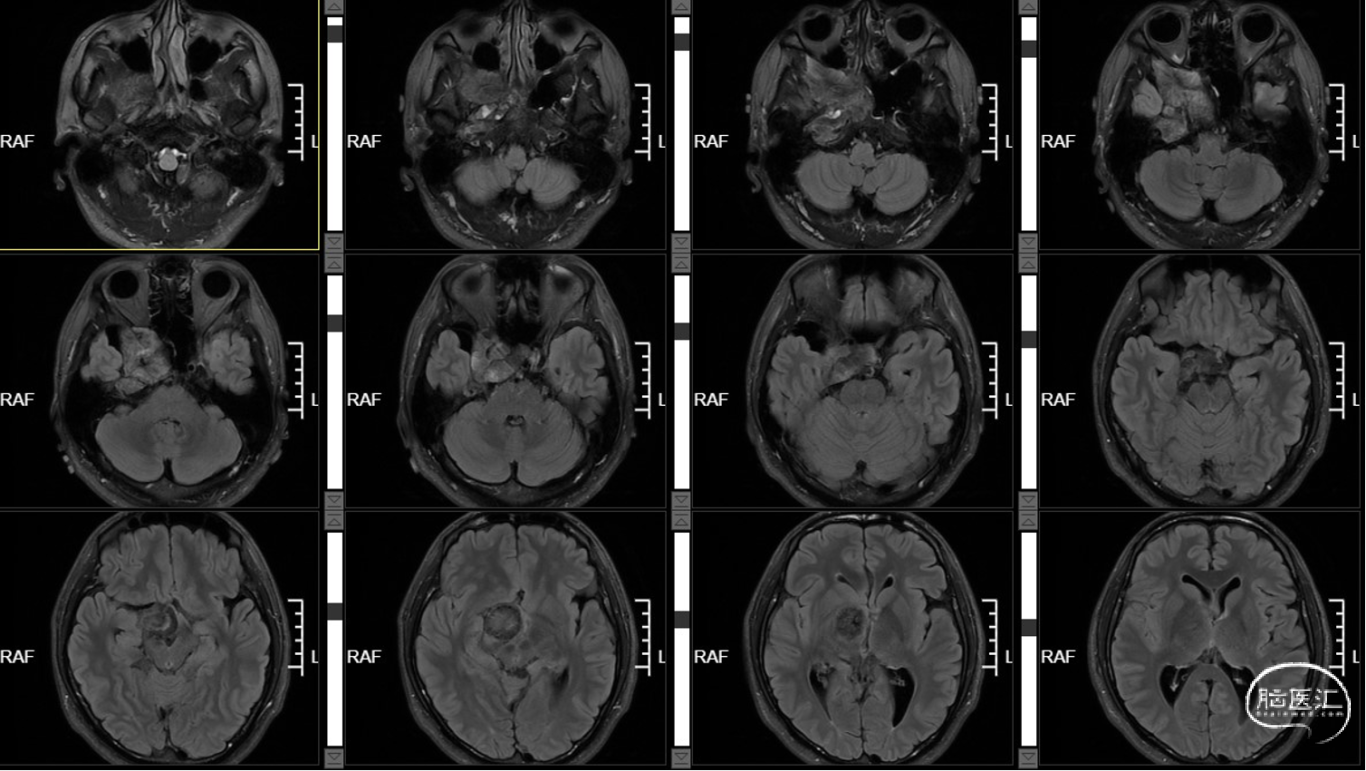

外院MR示:右侧颞底、桥小脑角区及鞍内占位,考虑表皮样囊肿伴破裂可能。